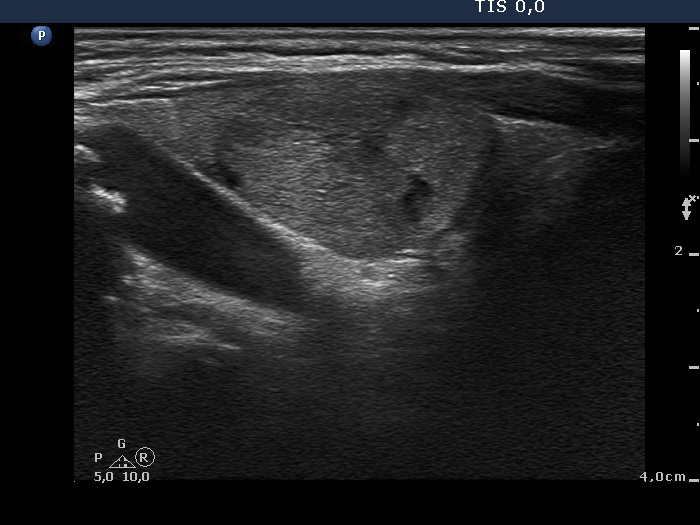

Clinical presentation: A 67-year-old woman was referred for aspiration cytology of a recurrent nodule. A left subtotal lobectomy was performed 19 years ago, histopathology resulted in benign lesion not otherwise specified. She noticed a rapidly growing mass in the right lobe which caused neck discomfort.

Palpation: a firm nodule in the right lobe.

Ultrasonography. The thyroid was echonormal. A large nodular area occupied great part of the right lobe. This area was composed of discrete lesions with different echogenicities. The nodular are presented signs of perinodular blood flow. There were small discrete lesions in the left lobe.

It is worth analyzing the ultrasound presentation. At first sight, a follicular tumor seems very likely: a large solitary nodule with halo sign occupies great proportion of a lobe. However, a more thorough analysis reveals that this large nodular area is composed of discrete lesions; although this feature does not exclude a follicular tumor, it significantly reduces this possibility.